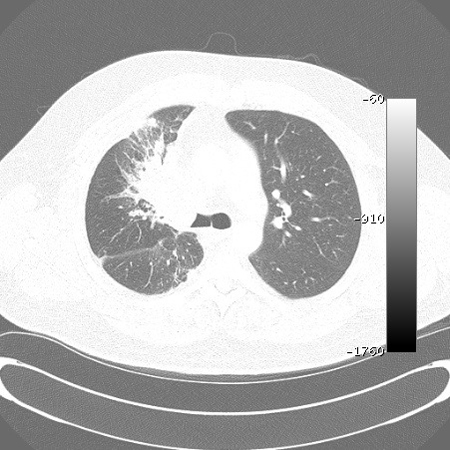

Malignant endobronchial obstruction on multidetector chest CT: lung window demonstrating right mainstem malignant obstruction

From the collections of Jose Fernando Santacruz MD, FCCP, DAABIP and Erik Folch MD, MSc; used with permission